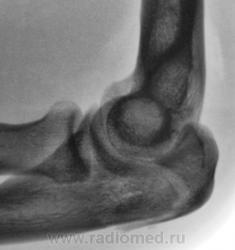

Травма.     Пациент направлен на рентгенографию локтевого сустава.

Перелом локтевого отростка - на операцию

Если рассуждать с точки зрения только диагностики перелома - нет, так как перелом хорошо виден и на стандартных проекциях. С точки зрения дальнейшей лечебной тактики - да. Так как косые проекции выявили безусловную необходимость оперативного лечения.